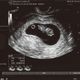

妊娠40週ころの超音波写真

骨盤の中に下りてきてお産の準備もOKです

成長した赤ちゃんや胎盤などで、子宮の中のスペースはいっぱいに。赤ちゃんは骨盤の中に下がってきて、お産に向けた体位になります。